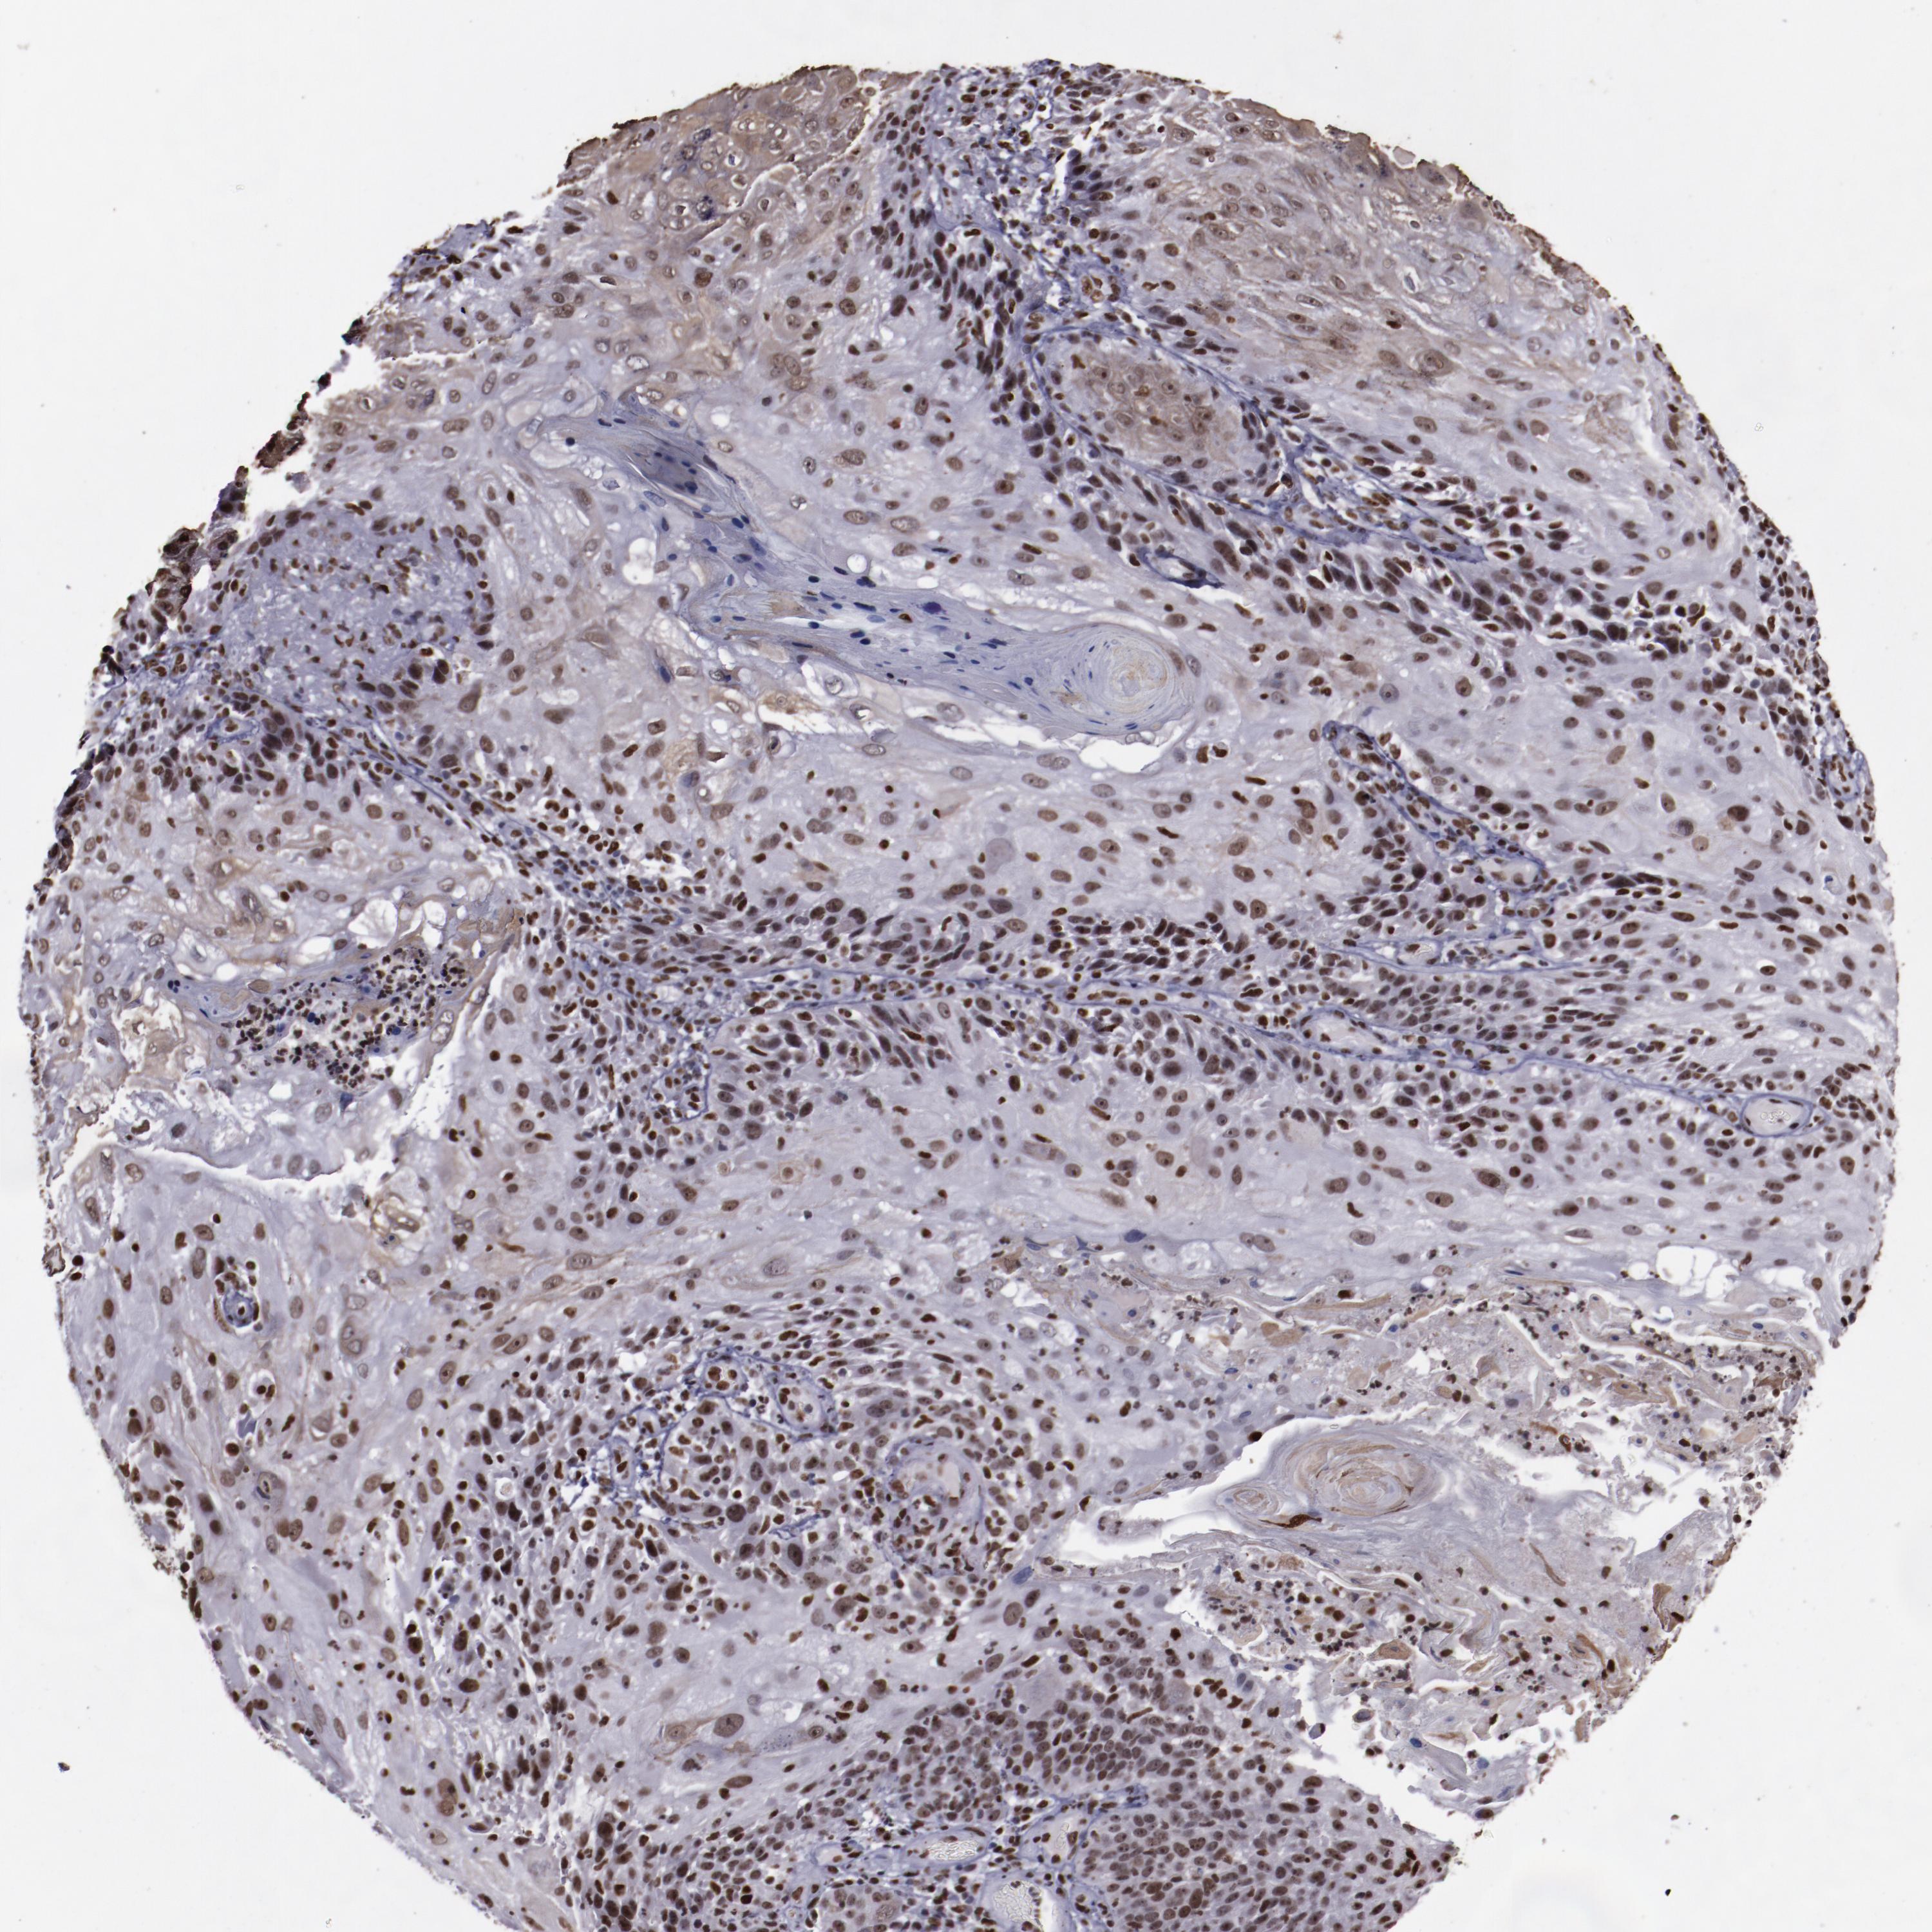

SKIN CANCER - Protein expressioni

A mouse-over function shows sample information and annotation data. Click on an image to view it in a full screen mode. Samples can be filtered based on level of antibody staining by selecting one or several of the following categories: high, medium, low and not detected. The assay and annotation is described here.

Each image is clickable and will lead to virtual microscopy that enables deeper exploration of all samples and also displays staining intensity scores, fraction scores and subcellular localization as well as patient and tissue information for each sample.

Antibody CAB047307

Staining

High

Medium

Low

Not detected

Intensity

Strong

Moderate

Weak

Negative

Quantity

>75%

75%-25%

<25%

None

Location

Nuclear

Cytoplasmic/membranous

Cytoplasmic/membranous,nuclear

Squamous cell carcinoma, metastatic, NOS